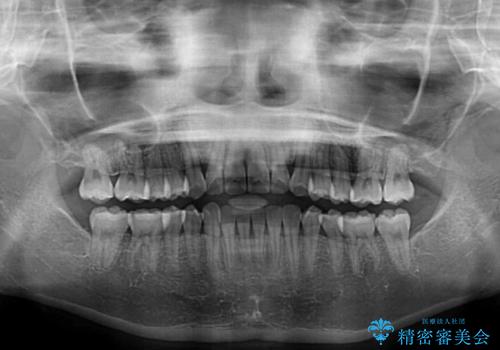

- 上下前歯のねじれを気にして来院された患者様です。

ワイヤー矯正でもマウスピース矯正でも対応可能でしたが、マウスピース矯正の自己管理が面倒であること、上顎前歯の捻転が著しいことから、ワイヤー矯正での治療を希望されました。